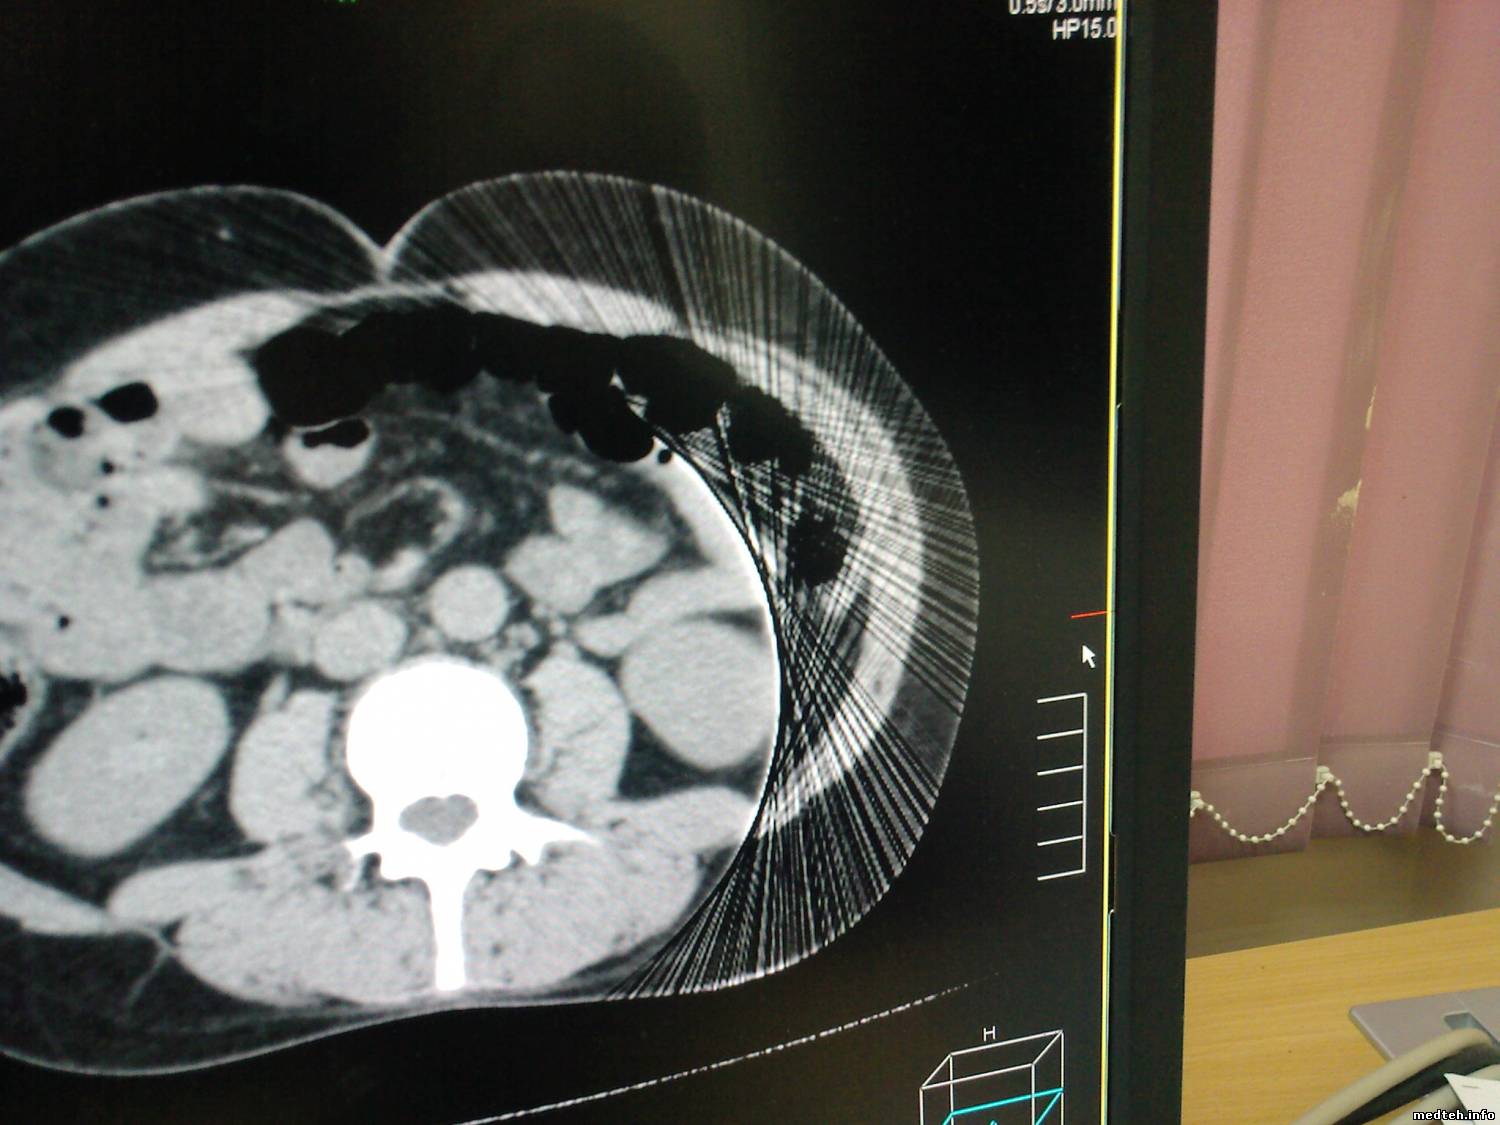

после подтопления кабинета, крыша протекла и по стенам пошли сырые разводы, на получаемых срезах появились "векторы направленности"

интересует момент - как объяснить грамотно проблему медперсоналу и что можно сделать на уровне пользователя?

4171846.jpg (133.2 Kb) · 4153610.jpg (204.8 Kb)